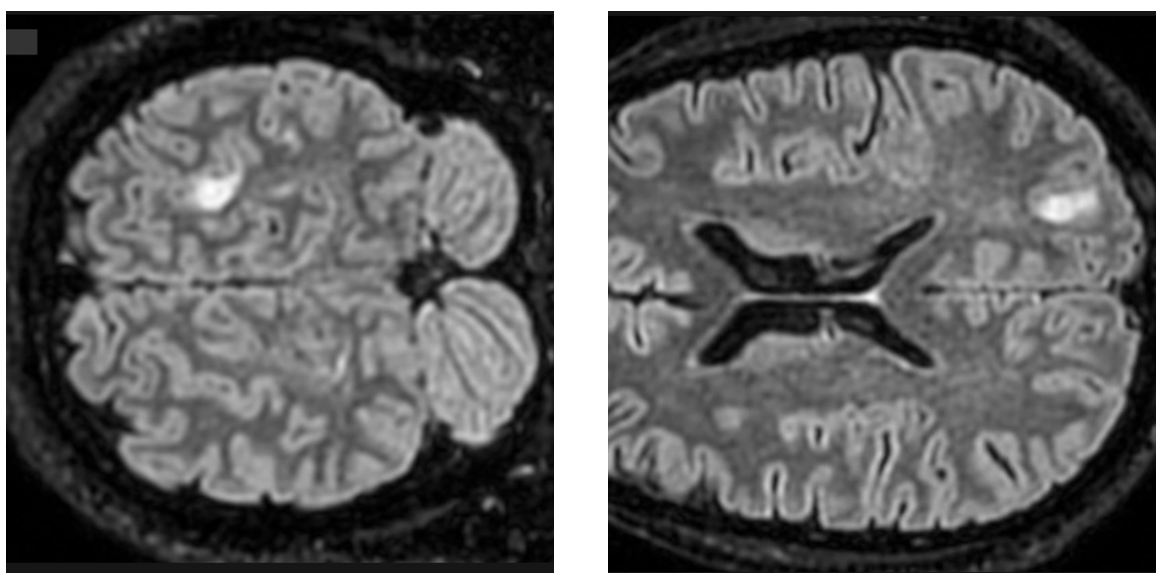

Adjunto el informe de RM cerebral con contraste. La conclusión describe múltiples focos bilaterales, con lesión cortical parietal posterior izquierda con captación en anillo sin restricción de difusión, y plantea como posibilidad una lesión neoplásica glial multifocal con foco de mayor agresividad parietal izquierdo, considerándose menos probable etiología infecciosa o desmielinizante. Solicito derivación preferente a Neurocirugía/Neuro-oncología para valoración de biopsia estereotáxica y planificación de pruebas complementarias (RM avanzada perfusión/espectroscopia o punción lumbar si procede).

Se adjuntan imágenes adicionales similares realizadas en una RMC previa de Febrero de 2026 en el Centro Medico Piramides de Sanitas: